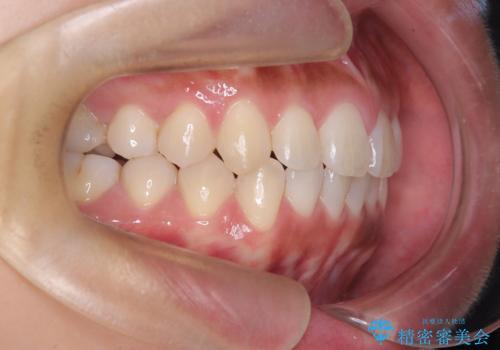

臼歯部の反対咬合を改善|MARPEによる上顎急速拡大+審美ワイヤー矯正

- 患者様は、奥歯(臼歯部)の反対咬合を主訴に来院されました。反対咬合は、噛み合わせのズレや顎の成長に影響を与える可能性があるため、早期の治療が重要です。診断の結果、上顎の幅が不足していることが原因と判明し、MARPE(骨固定式上顎急速拡大装置)を用いて上顎を広げる治療を計画しました。その後、歯列の調整のために審美ワイヤー矯正を行う方針としました。

MARPEを使用して上顎を拡大し、適切な歯列のスペースを確保しました。この拡大によって、反対咬合が改善され、正常な噛み合わせへと誘導できました。その後、目立ちにくいブラケットと白いワイヤーを使用した審美ワイヤー矯正を行い、歯列を整えました。治療が進むにつれ、噛み合わせのバランスが良くなり、見た目も自然な仕上がりに。